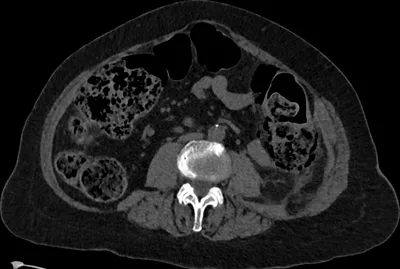

Perforation Radiology Images

This collection contains 1 radiology images related to perforation, including various imaging modalities such as X-rays, MRIs, CT scans, and ultrasound images commonly used in medical diagnosis and education.